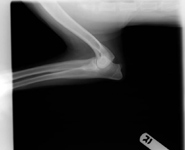

Otras pruebas de diagnóstico para ayudar a diferenciar las causas de la patología del codo son la artrocentesis, las imágenes y la artroscopia. Las radiografías son de poco valor en la identificación del fragmento o la línea de separación vista con el clásico FMCP o TFMCP (Foto 1). Las técnicas más avanzadas de imágenes como la tomografía computarizada, la resonancia magnética y la artroscopia pueden ayudar a confirmar la condición. La evaluación artroscópica de la articulación del codo tiene las siguientes ventajas: la observación directa y el aumento de todas las principales estructuras intra-articulares, la evaluación dinámica de los tejidos durante los ejercicios de rango de movimiento y la palpación de los tejidos intra-articulares con instrumentos para artroscopía. En consecuencia, la exploración artroscópica definitivamente puede ayudar a diagnosticar TFMCP cuando se observa un fragmento o fisura de cartílago (Foto 2). En un pequeño porcentaje de casos, las imágenes avanzadas (tomografía computarizada, resonancia magnética) indican la fragmentación de la coronoides no vista con la artroscopia. En tales casos, se cree que las microfracturas están dentro del hueso coronoides por debajo de la superficie del cartílago.